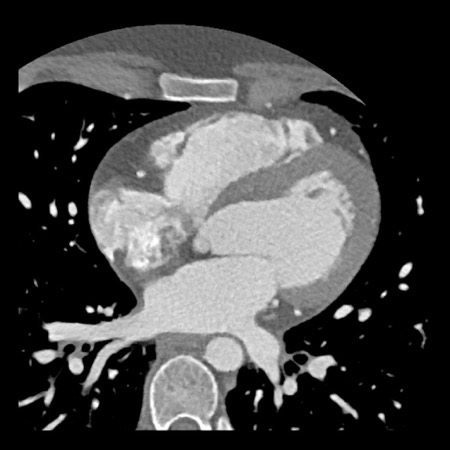

case 3 – Calcium score 0 and severe stenoses.

First, scroll through the CTA images.

How would you describe the findings on the coronary CTA?

The findings are:

- The total calcium

score of 0 indicates the absence of calcified plaque in the coronary

tree. - Severe stenosis

(70-99%) in the mid LAD and D2 branch.

Continue with the next images of the same patient…

Same patient. First, study the CTA image.

How would you describe the findings?

The coronal image shows a central low-attenuation area around the lumen

of the LAD.

This low-attenuation area is surrounded by a higher attenuation

area.

This finding is the earlier discussed napkin-ring sign, which is a high-risk

plaque feature.

This patient classifies as CAD-RADS 4A/P1/HRP.